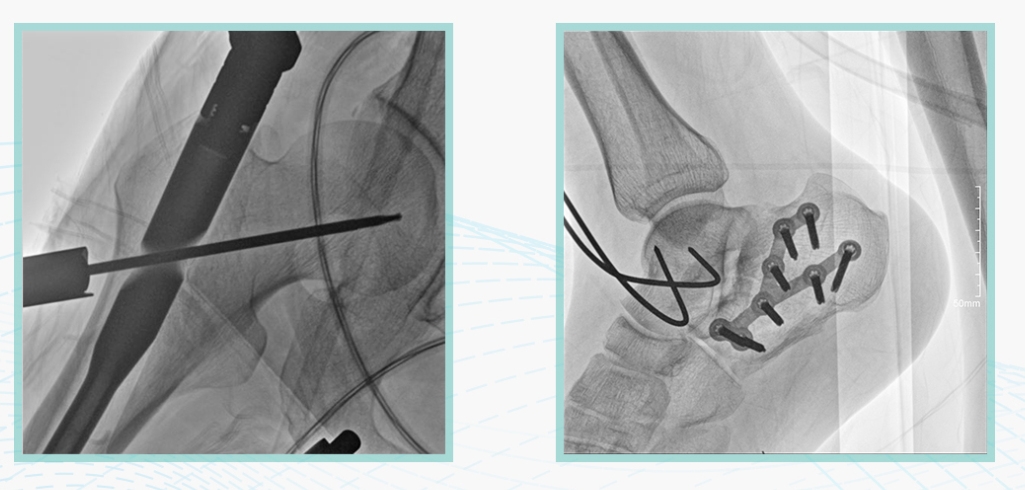

德赢VWIN科技悦画移动C臂X线摄影系统,采用了业内技术最尖端的CMOS探测器。基于性能优异的针状CSI闪烁体涂层和高灵敏度的CMOS感光芯片,悦画可以实现在超低X线剂量条件下实现高清晰影像成像,相较于一般的影增移动C臂和平板C臂,动态范围更高,影像的层次感和对比度更好。

在产品的性能参数设计上,悦画的像素可达到200万,空间分辨率可达到3.2线对,采用16bit的影像灰度,悦画在影像后处理上,通过SPI金字塔图像算法,支持摄影、脉冲透视影像、连续透视等多种模式下的影像采集,动态透视影像视频支持保存与回放。双大屏的设计,透视影像支持三档放大,保证临床影像读取的便利。

悦画在影像的伪影处理上,也积累多项图像处理专利技术。通过对植入物的精准识别,悦画能够精准祛除植入物伪影与运动伪影,保证高质量的影像输出,无论是影像的对比度、分辨率(清晰度)相较于市面上的移动C臂产品都更胜一筹。